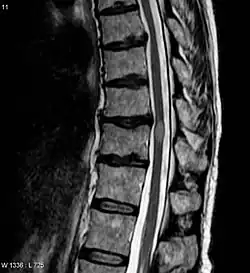

| Acute myelitis | intramedullary lesion > 3 contiguous segments, or spinal atrophy ≥ 3 contiguous segments |

In NMOSD, areas of brain tissue that appear normal in conventional magnetic resonance imaging (MRI) can show damage in diffusion tensor imaging (DTI), although less so compared to multiple sclerosis (MS).[25]

The clinical course and the response to therapy is different for various diseases classed within these groups, showing a better prognosis for those in the NMO-Ab(−)/MOG-Ab(−) group, and a worse prognosis for those in the NMO-Ab(+)/MOG-Ab(+) group.[30] The MOG-related NMO can be radiologically identified by the conus involvement. Myelin-oligodendrocyte glycoprotein antibody–positive patients were more likely to have conus involvement on spinal magnetic resonance imaging.[31]